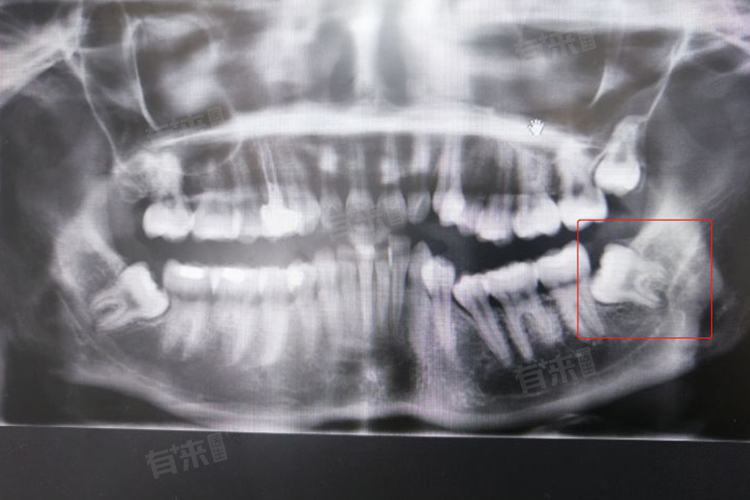

- 如果智齿的萌出位置和方向不正确,或者没有对颌牙、上下颌牙齿的咬合关系不良、智齿本身有龋坏、引起邻牙龋坏、长期引起反复的智齿冠周炎,都建议拔除。在智齿的拔除手术前,通常需要进行全口牙齿X线片或者锥形束CT检查,以评估智齿的位置、大小、形态等,以及与周围结构(如下颌神经和上颌窦)的关系。